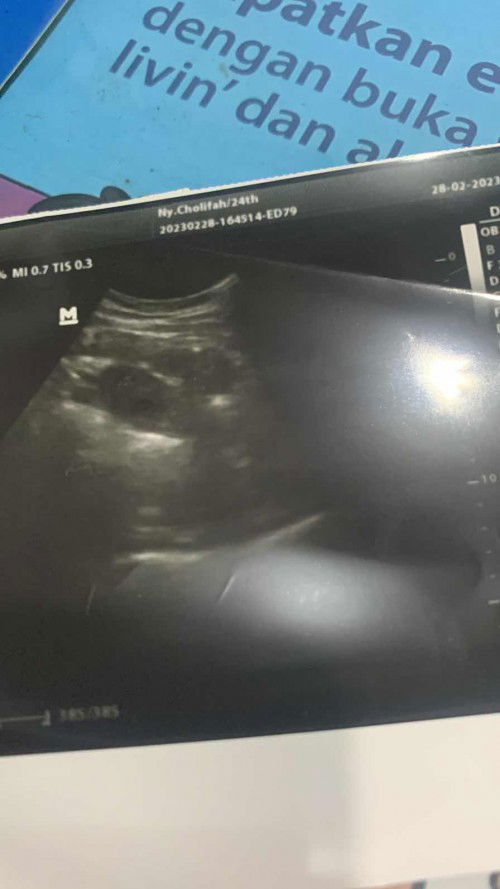

sepertinya 2 kantong bun, duh senangnyaaa. semoga bulan depan lebih jelas yah bun.